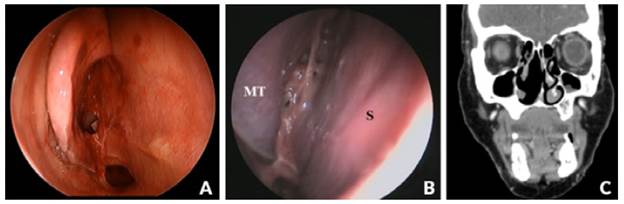

A 43-year old Caucasian female patient, teacher, with no relevant medical history, presented to our hospital with complaints of right nasal obstruction of 6 months of evolution, associated with mucopurulent rhinorrhea and recurrent right side epistaxis. Physical examination showed a right obstructive mass originating from the roof of the nasal fossa (cribriform plate), which caused a deviation of the nasal septum to the left and a lateralization of the middle turbinate to the right (Figure 1A).

(A) Rhinoscopy: Obstructive mass originating from the roof of the right nasal fossa. HPC - Hemangiopericytoma, S -Nasal Septum, MT - Middle Turbinate; (B) CT paranasal sinuses in soft tissue window (coronal); (C) endoscopic surgery.

Figure 1: (A) Rhinoscopy: Obstructive mass originating from the roof of the right nasal fossa. HPC - Hemangiopericytoma, S -Nasal Septum, MT - Middle Turbinate; (B) CT paranasal sinuses in soft tissue window (coronal); (C) endoscopic surgery.

Computed tomography of the paranasal sinuses (CT-PS) revealed a complete blockage of the right nasal cavity by a homogeneous content, with soft tissue density, without evident contrast enhancement. This neoformation caused bulging with thinning and remodeling of the septum and the wall of the right maxillary sinus. The lesion extended superiorly to the cribriform plate but without intracranial or orbital extension, and posteriorly through the choana to the nasopharynx (Figure 1B). CT scan of the neck and thorax did not identify relevant alterations. A biopsy of the lesion was performed and the histological study revealed an inflammatory polyp with no signs of malignancy.

The patient underwent endoscopic surgery with en bloc resection of the lesion that originated in the cribriform plate of the ethmoid (Figure 1C), without sequelae associated with the procedure.